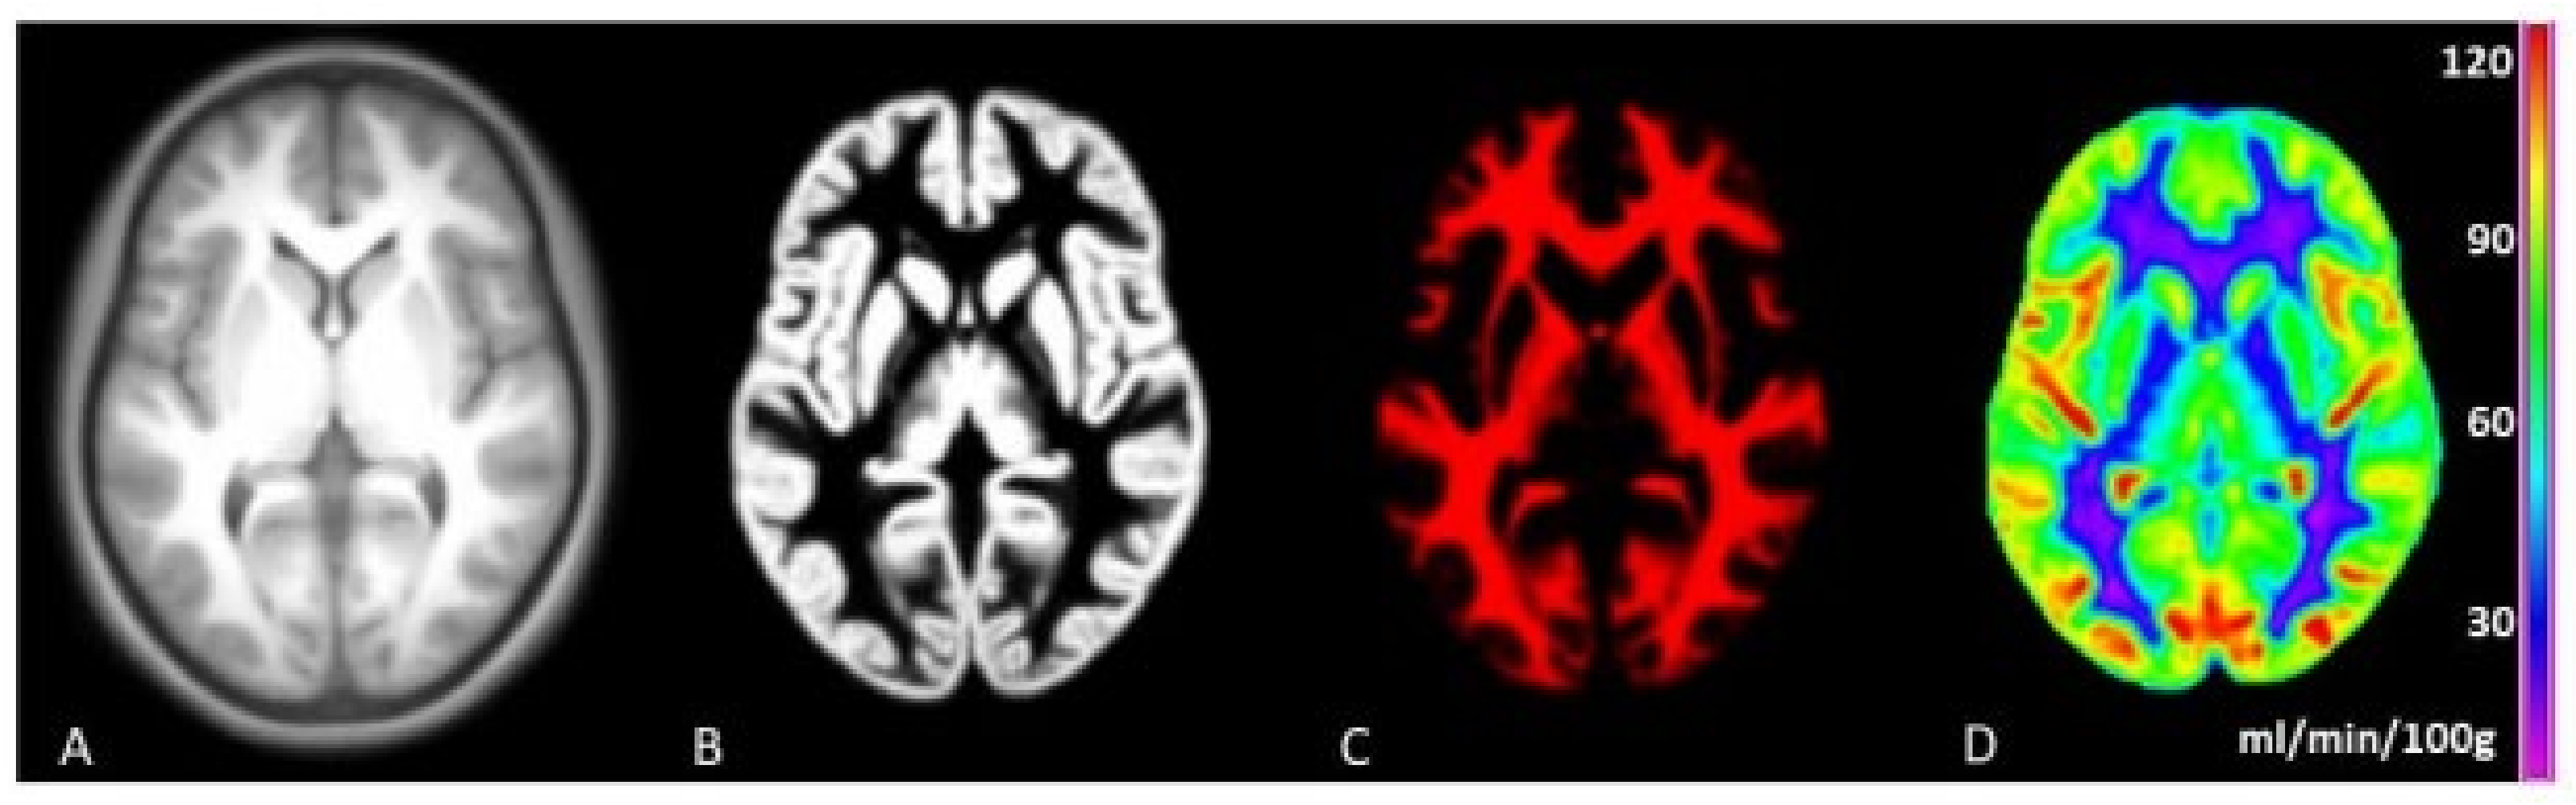

- Mutsaerts, H.J.M.M.; Petr, J.; Groot, P.; Vandemaele, P.; Ingala, S.; Robertson, A.D.; Václavů, L.; Groote, I.; Kuijf, H.; Zelaya, F.; et al. ExploreASL: An image processing pipeline for multi-center ASL perfusion MRI studies. Neuroimage 2020, 219, 117031. [Google Scholar] [CrossRef]